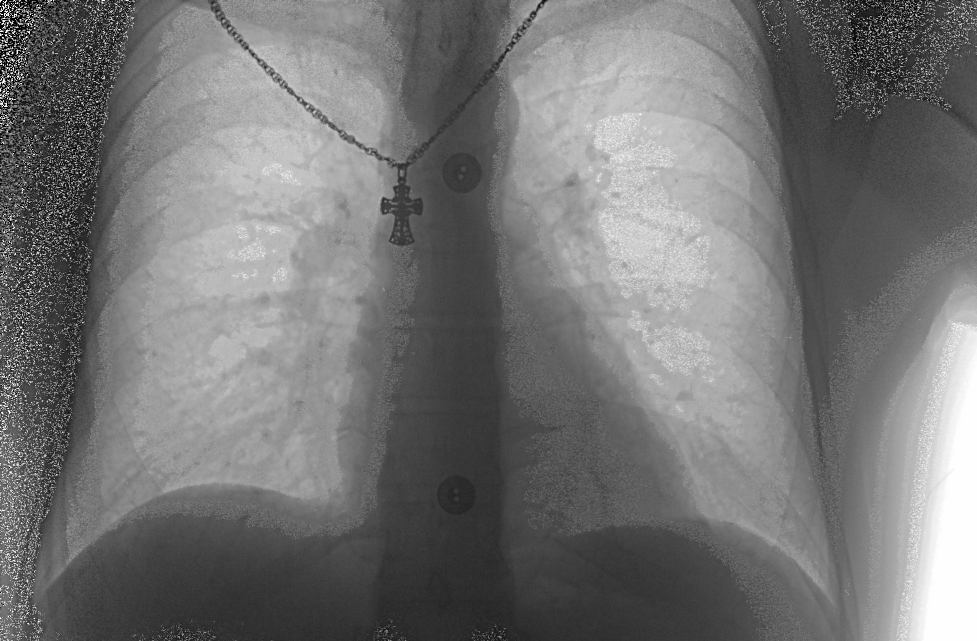

Вот кстати тестер снятый с экспонометром 100 кВ 0,5 мАс. Да и еще - строители умудрились повредить кабель "Камера-граббер". Пришлось его укорачивать и перепаивать разъем.

1579436.bmp (1.79 Mb)

Вот кстати тестер снятый с экспонометром 100 кВ 0,5 мАс

А что за режим дурацкий.

Переведите мАсы на время.

Даже при 100 мА время 0.005с.

Бред какой то.

Поставьте 70 кВ и 8 мАс.

На снимках пациентов по всей видимости тот же бред.

Quote (АГИ)

что за режим дурацкий

Оценка высказана в грубой форме, но вынужден присоединиться, поскольку 100 кВ в прямом пучке и для камеры и для экспонометра - слишком круто.

Для тестера и этого много будет.

По поводу тестера - согласен. Но легкие? Режимы выставлены по рекомендациям электроновцев.Снимки до пожара - режимы аналогичные 100 кВ прямые около 10 мАс, боковые около 16 мАс. Рекомендовали откалибротваь трубку - не помогло. При калибровке камеры в tunerxp, например при калибровке фона когда работает одна камера без высокого картинка получается будто бы присыпанная манной крупой. Множество точек на черном фоне. Как должно быть пока не ясно. Поищу другой аппарат и посмотрю какой фон должен при калибровке камеры.